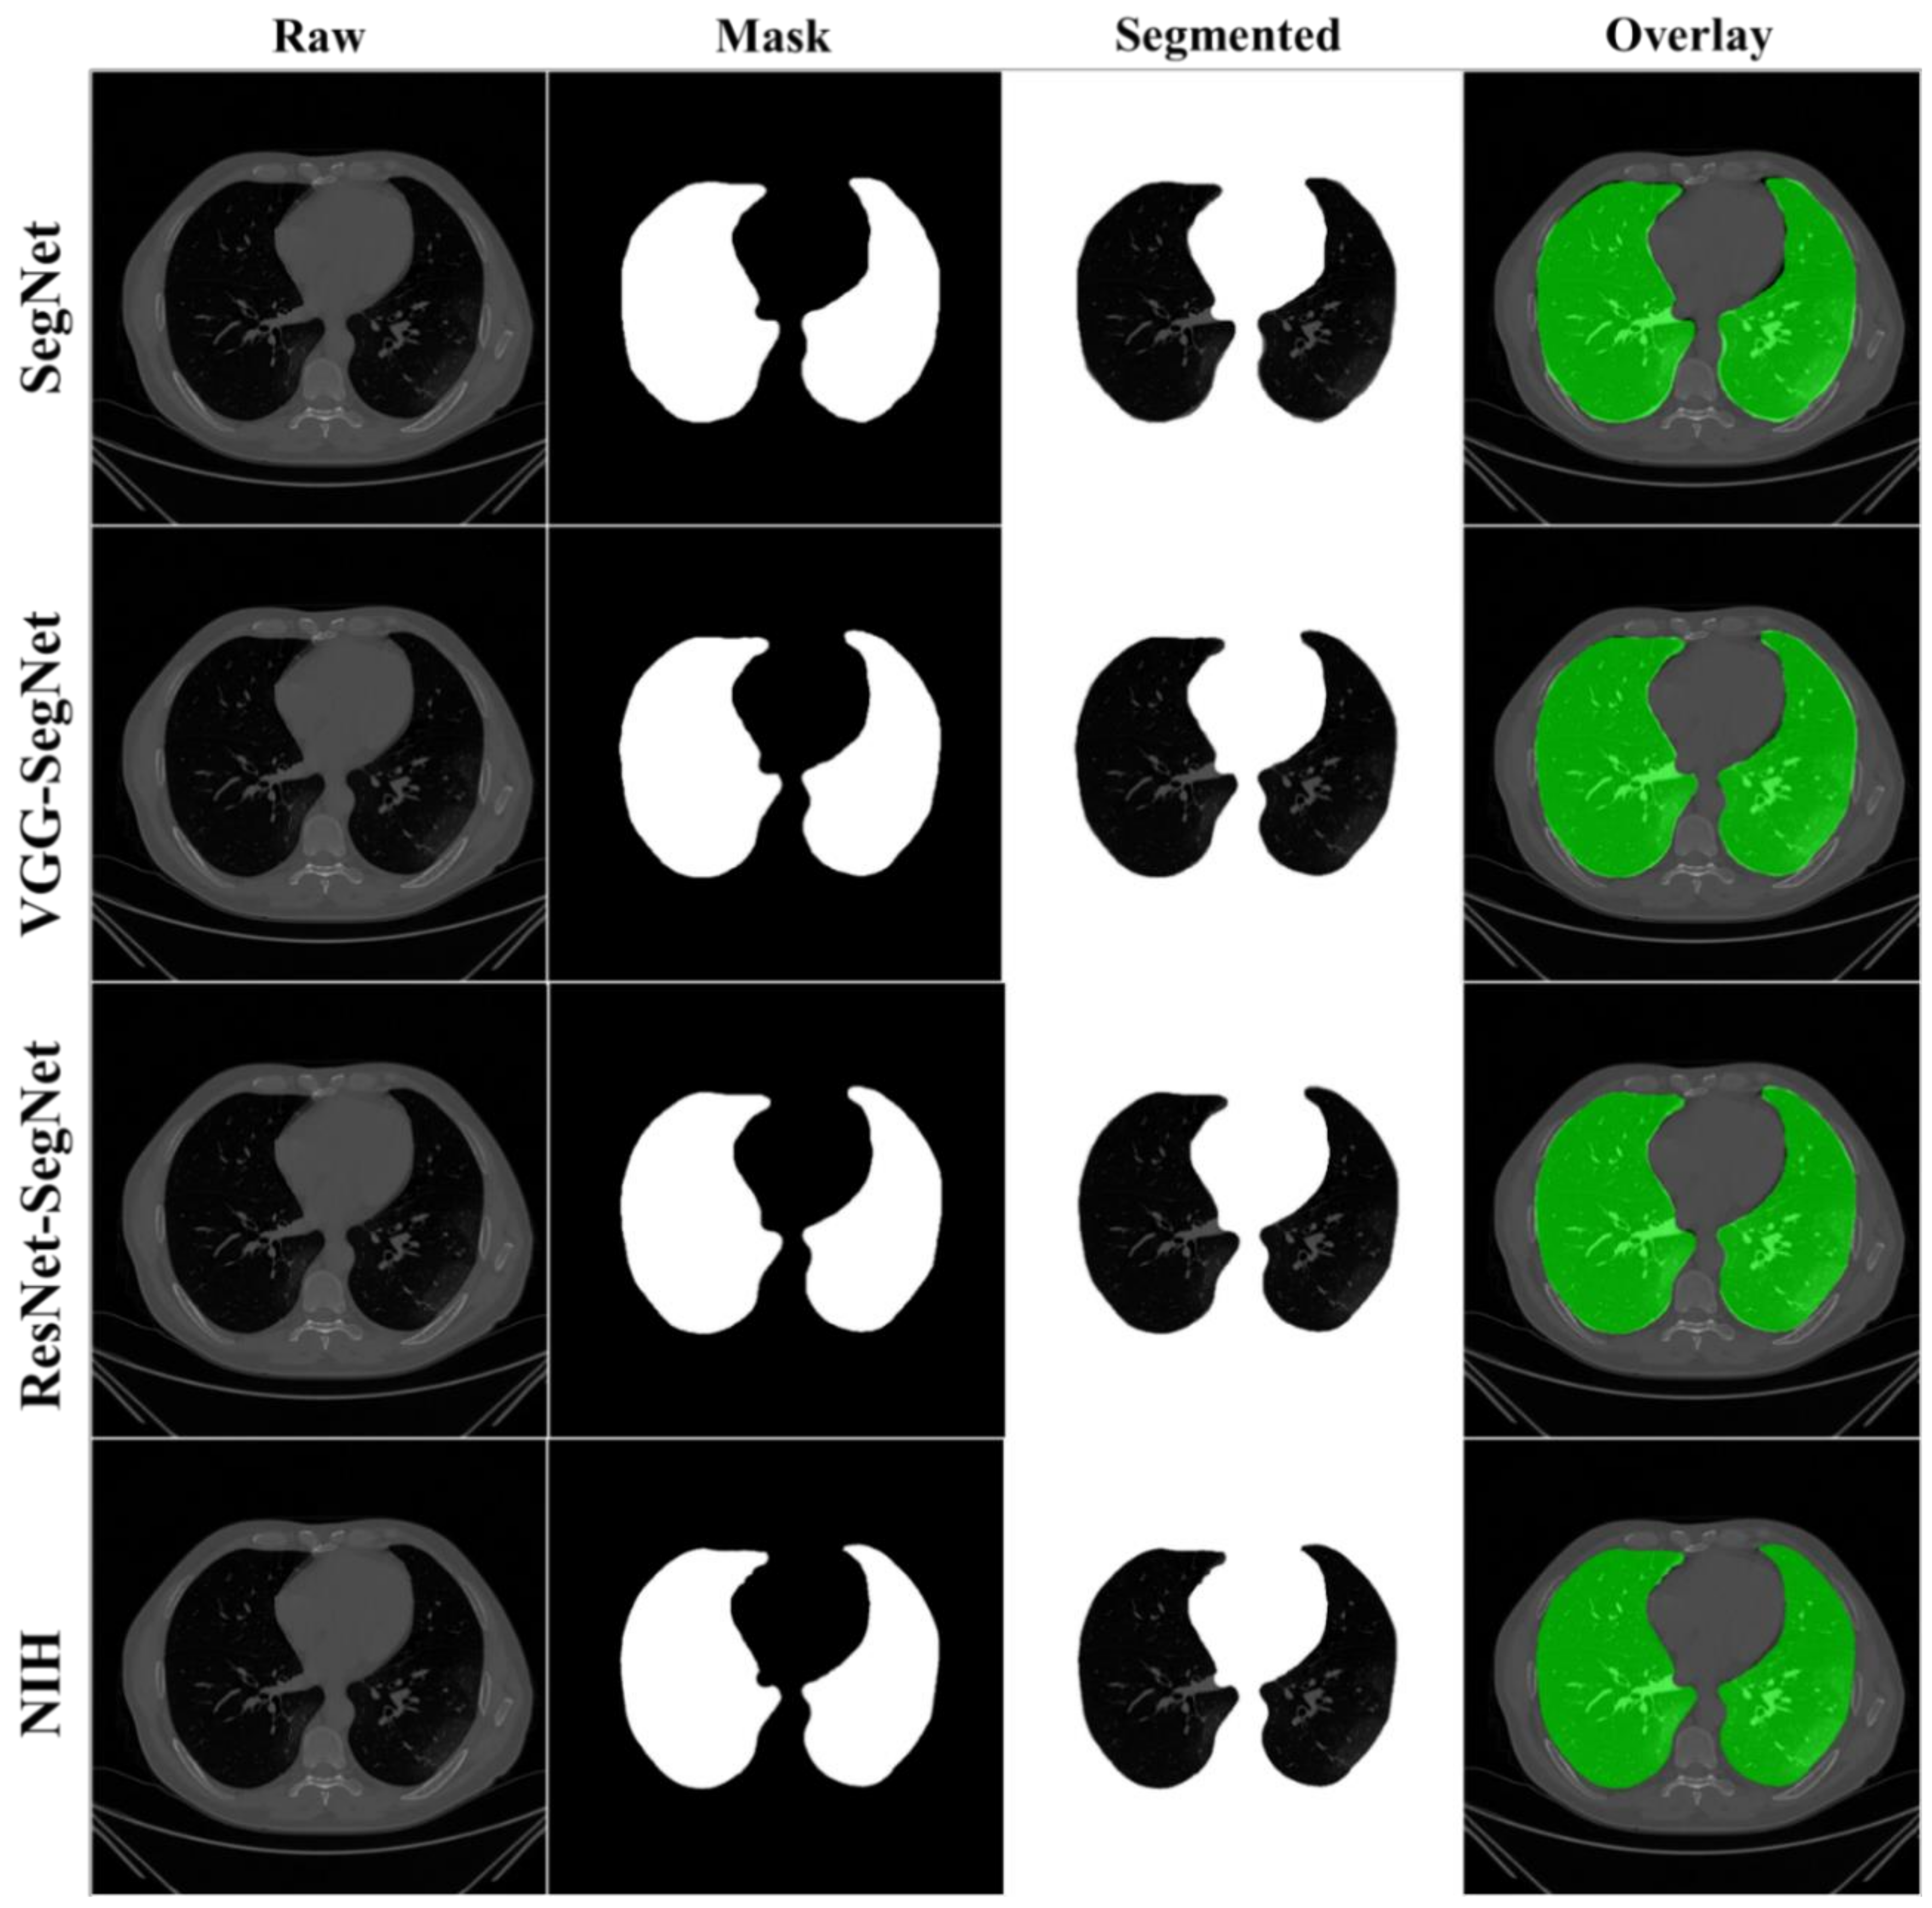

4.1. Results

4.2. Performance Evaluation

4.2.1. Visualization of Lung Boundary and Regional Lung Error